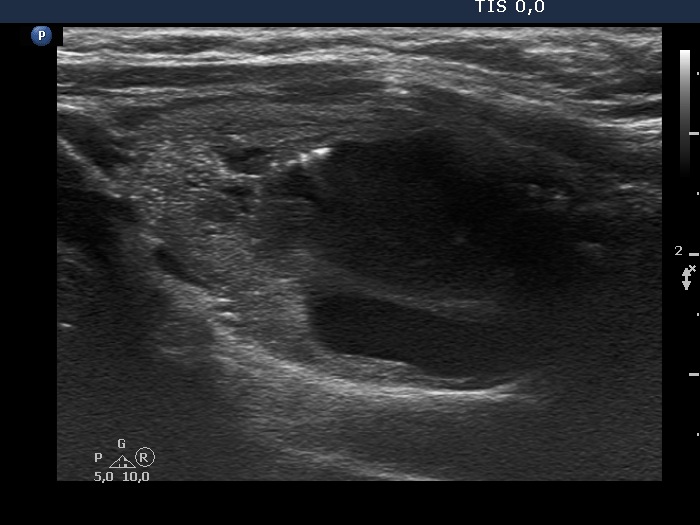

The composition of the nodule - case 491

Examination 3 years later (ultrasonographic picture 7)

Left lobe, longitudinal scan - 30 seconds after aspirating 5 ml bloody fluid. The nodule has regained its orginal size.